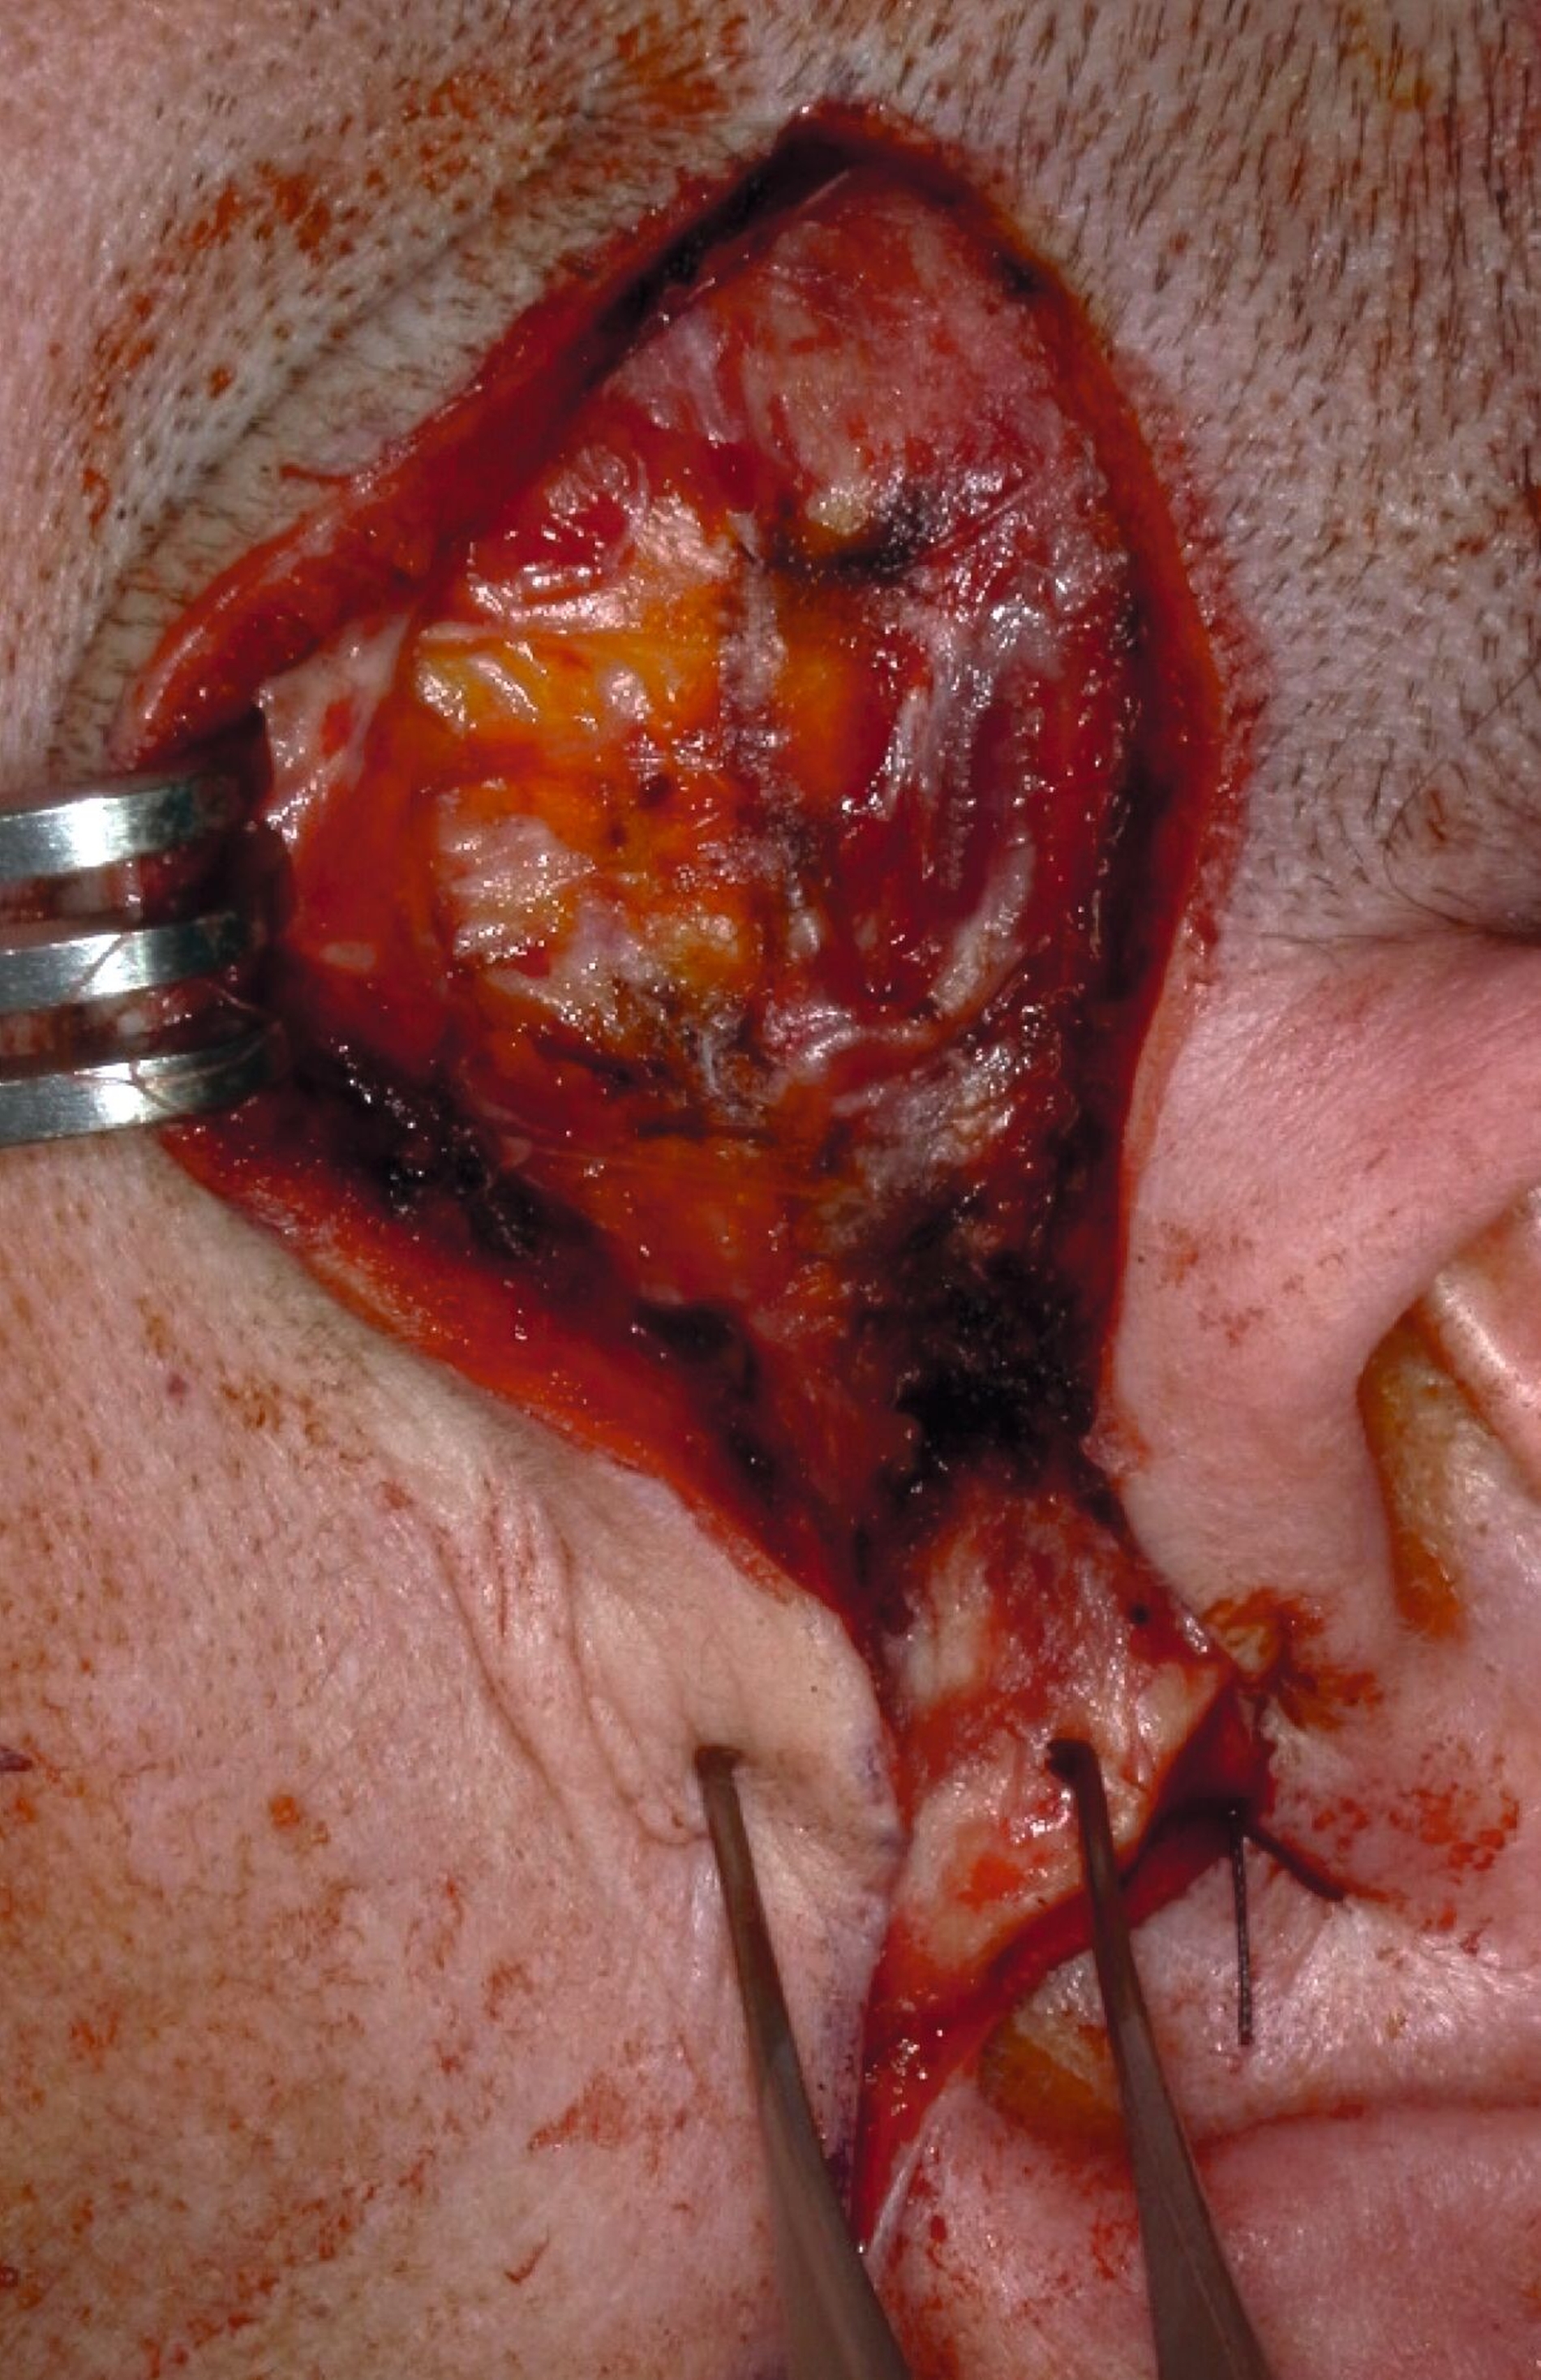

Klinisch zeigte sich kein Hinweis auf eine Myopathie der Kaumuskulatur. Zudem waren weder eine Mundöffnungsbehinderung noch ein Kiefergelenkgeräusch detektierbar. In Anbetracht der klinischen und der radiologischen Verdachtsdiagnose wurde eine Magnetresonanztomografie durchgeführt (Abbildung 2), die eine deutliche Flüssigkeitskollektion zirkulär im Bereich des linken Kiefergelenks mit multiplen, a. e. hyalinen Fragmenten sichtbar macht.

Bei nunmehr erhärteter radiologischer Verdachtsdiagnose auf das Vorliegen einer synovialen Chondromatose erfolgte, entsprechend dem Patientenwunsch, die offen-chirurgische Resektion der multiplen Gelenkkörper in Intubationsnarkose. Der Zugang wurde klassisch präaurikulär mit einer temporalen Extension zum Schutz des Ramus temporalis des Nervi facialis gewählt (Abbildung 3a). Unmittelbar nach Eröffnung der Kiefergelenkkapsel entleerten sich rasch mehrere kleine, knorpelige Raumforderungen (Abbildung 3b), die im Rahmen des Eingriffs vollständig entfernt wurden (Abbildung 3c). Der erweiterte, nun leere obere Gelenkspalt ist in Abbildung 3d dargestellt.